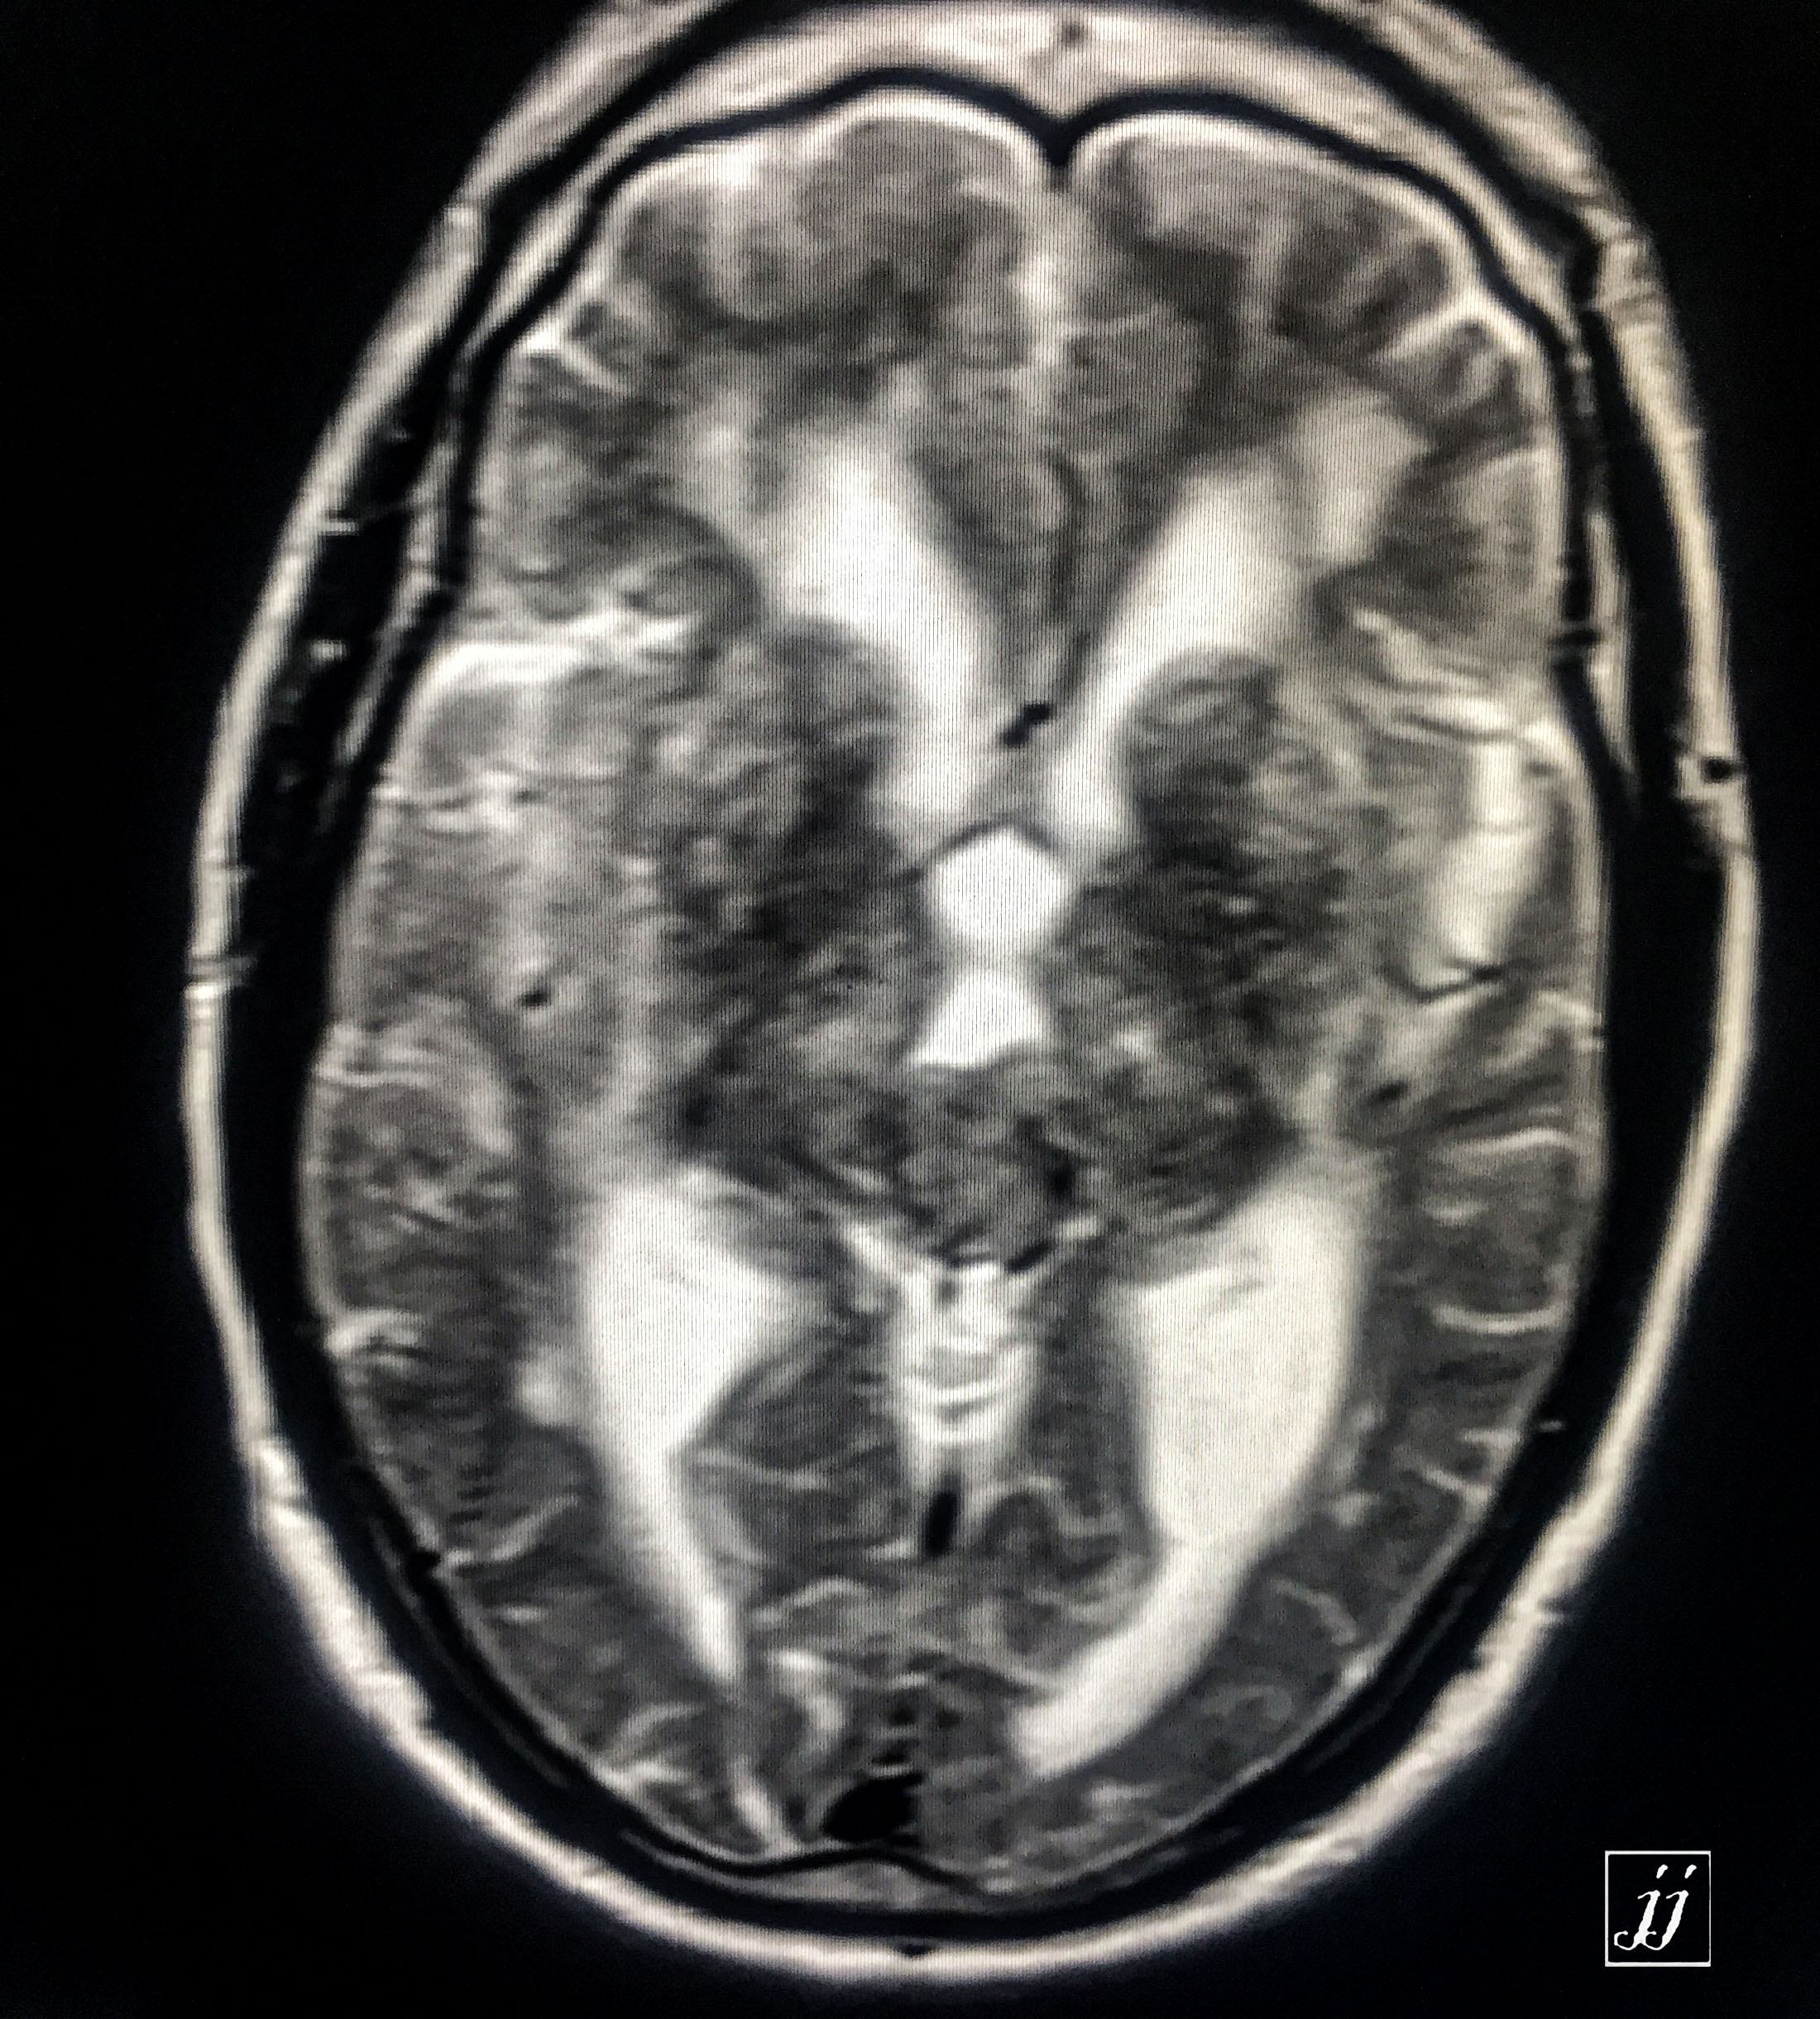

Brain- quadrigeminal tectal meningioma and hydrocephaly (3)